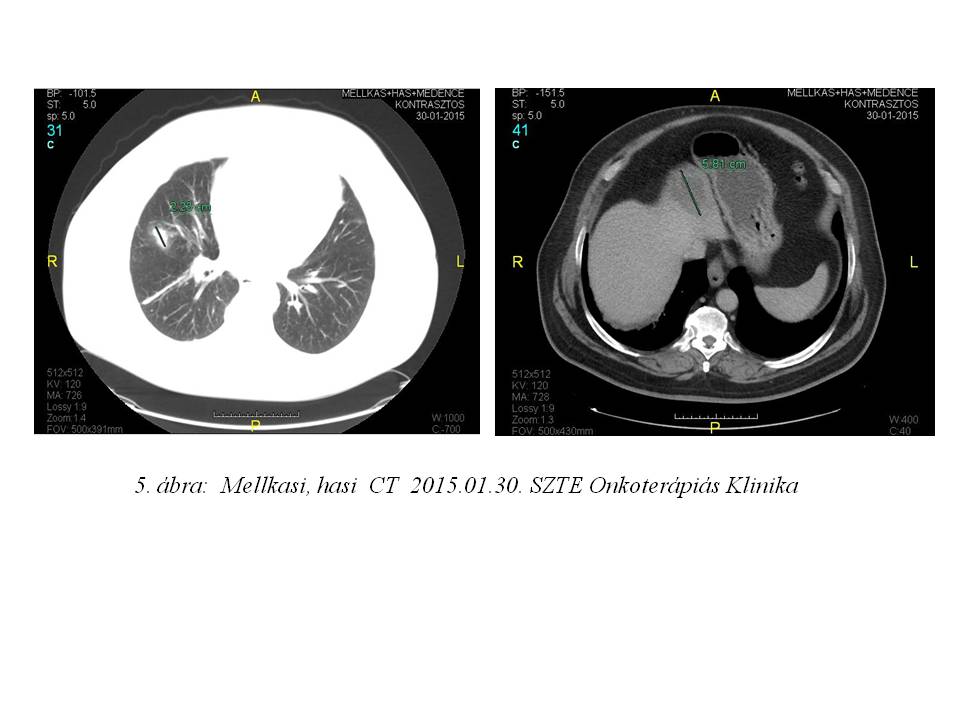

Az első staging mellkasi CT vizsgálat 3 hónap után részleges regressziót írt le (3. ábra), majd további javulást figyelhettünk meg (4. ábra, 5. ábra).

Az esetünket öszefoglalva: betegünk eddig 17 ciklus sorafenib kezelést kapott. Teljes dózisú terápia mellett csak grade I-es, jól tolerálható mellékhatások jelentkeztek. A tüdő áttétek valamint a mediastinalis és hilusi lymphadenomegalia részleges regressziója már 3 hónap kezelés után bekövetkezett.